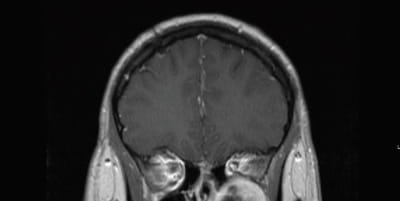

Coronal T1 post contrast MRI demonstrating the left sided schwannoma centered within the pterygopalatine fossa. Inferior orbital compression is demonstrated.Coronal T1 post contrast MRI demonstrating the left sided schwannoma centered within the pterygopalatine fossa. Inferior orbital compression is demonstrated.